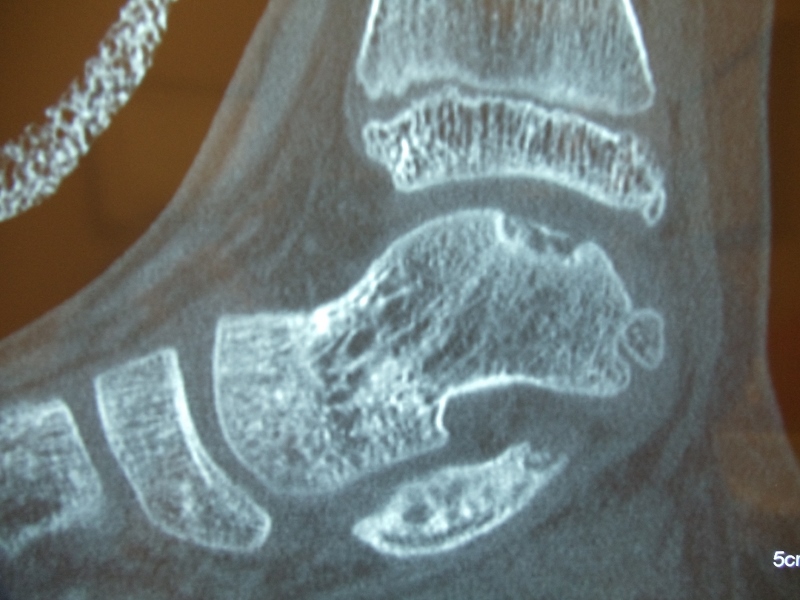

Intraop arthroscopic pics of talar OCD surgery.

A series of intraop ankle arthroscopy pics of synovial chondromatosis with OCD talus and tibia and microfracture.